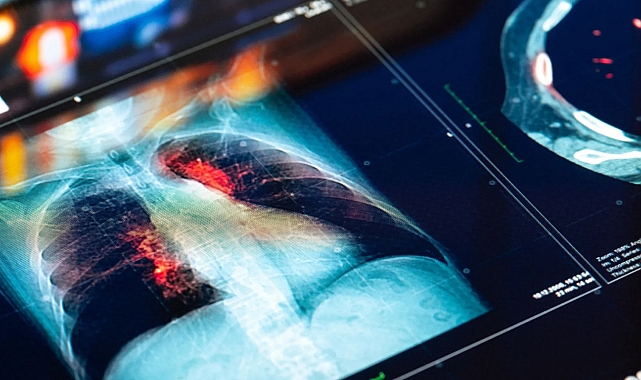

Royal Marsden NHS, Imperial College ve Londra Kanser Araştırmaları Enstitüsü’ndeki uzmanlar tarafından tasarlanan yapay zekâ aracı, CT taramalarında bulunan anormal gelişimlerin kanserli olup olmadığını belirleyebiliyor. Araştırmaya göre, algoritma mevcut yöntemlerden daha verimli ve etkili bir performans sergiliyor. Bulgular eBioMedicine dergisinde yayınlandı. Royal Marsden'da klinik onkoloji uzmanı ve Imperial'da klinik araştırma görevlisi olan Dr. Benjamin Hunter, “Gelecekte, yüksek riskli hastaları belirleyerek ve onları daha erken müdahaleye hızlı bir şekilde yönlendirerek, erken teşhisi kolaylaştıracağını, potansiyel olarak kanser tedavisini daha başarılı hâle getireceğini umuyoruz” diyor.

Ekip, yapay zekâ algoritması geliştirmek için büyük akciğer nodülleri olan yaklaşık 500 hastanın CT taramalarını kullandı. Bu teknik, insan gözüyle kolayca fark edilemeyen görüntülerden hayati bilgiler ortaya çıkarabiliyor. Yapay zekâ modeli, kanserli nodülleri doğru bir şekilde tespit edip edemeyeceğini belirlemek için test edildi. Sonuçlar, YZ modelinin her bir nodülün kanser riskini 0.87 AUC ile belirleyebildiğini gösterdi. Performans, şu anda kullanılan ve 0.67 puan alan Brock testinin skorundan çok daha iyi. Model ayrıca 0.83 AUC değerine sahip bir başka test olan Herder skoru ile de yakın bir performans sergiledi.

YZ modeli, Herder ile birleştirildiğinde ise gruptaki yüksek riskli hastaları belirleyebildi. Çalışmaya göre, kanserli olduğu teyit edilen 22 nodülden 18'i (yüzde 82) için erken müdahale önerdi. Araştırmacılar YZ aracının, hastaların tedaviye hızlı bir şekilde yönlendirilmesine yardımcı olarak CT taramalarının analizini kolaylaştırmasını ve kanser tespitini hızlandırmasını umuyor.Kaynak: Mashable Türkiye